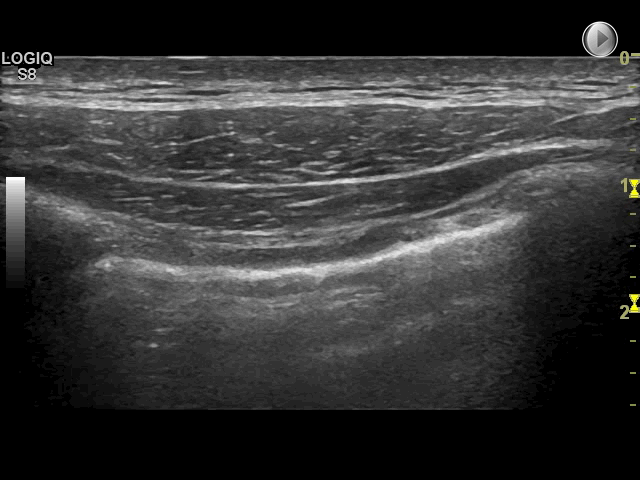

Top: Normal lung with sliding and B-lines present.

Bottom: No sliding, no lung pulse, and no B-lines — possible pneumothorax.